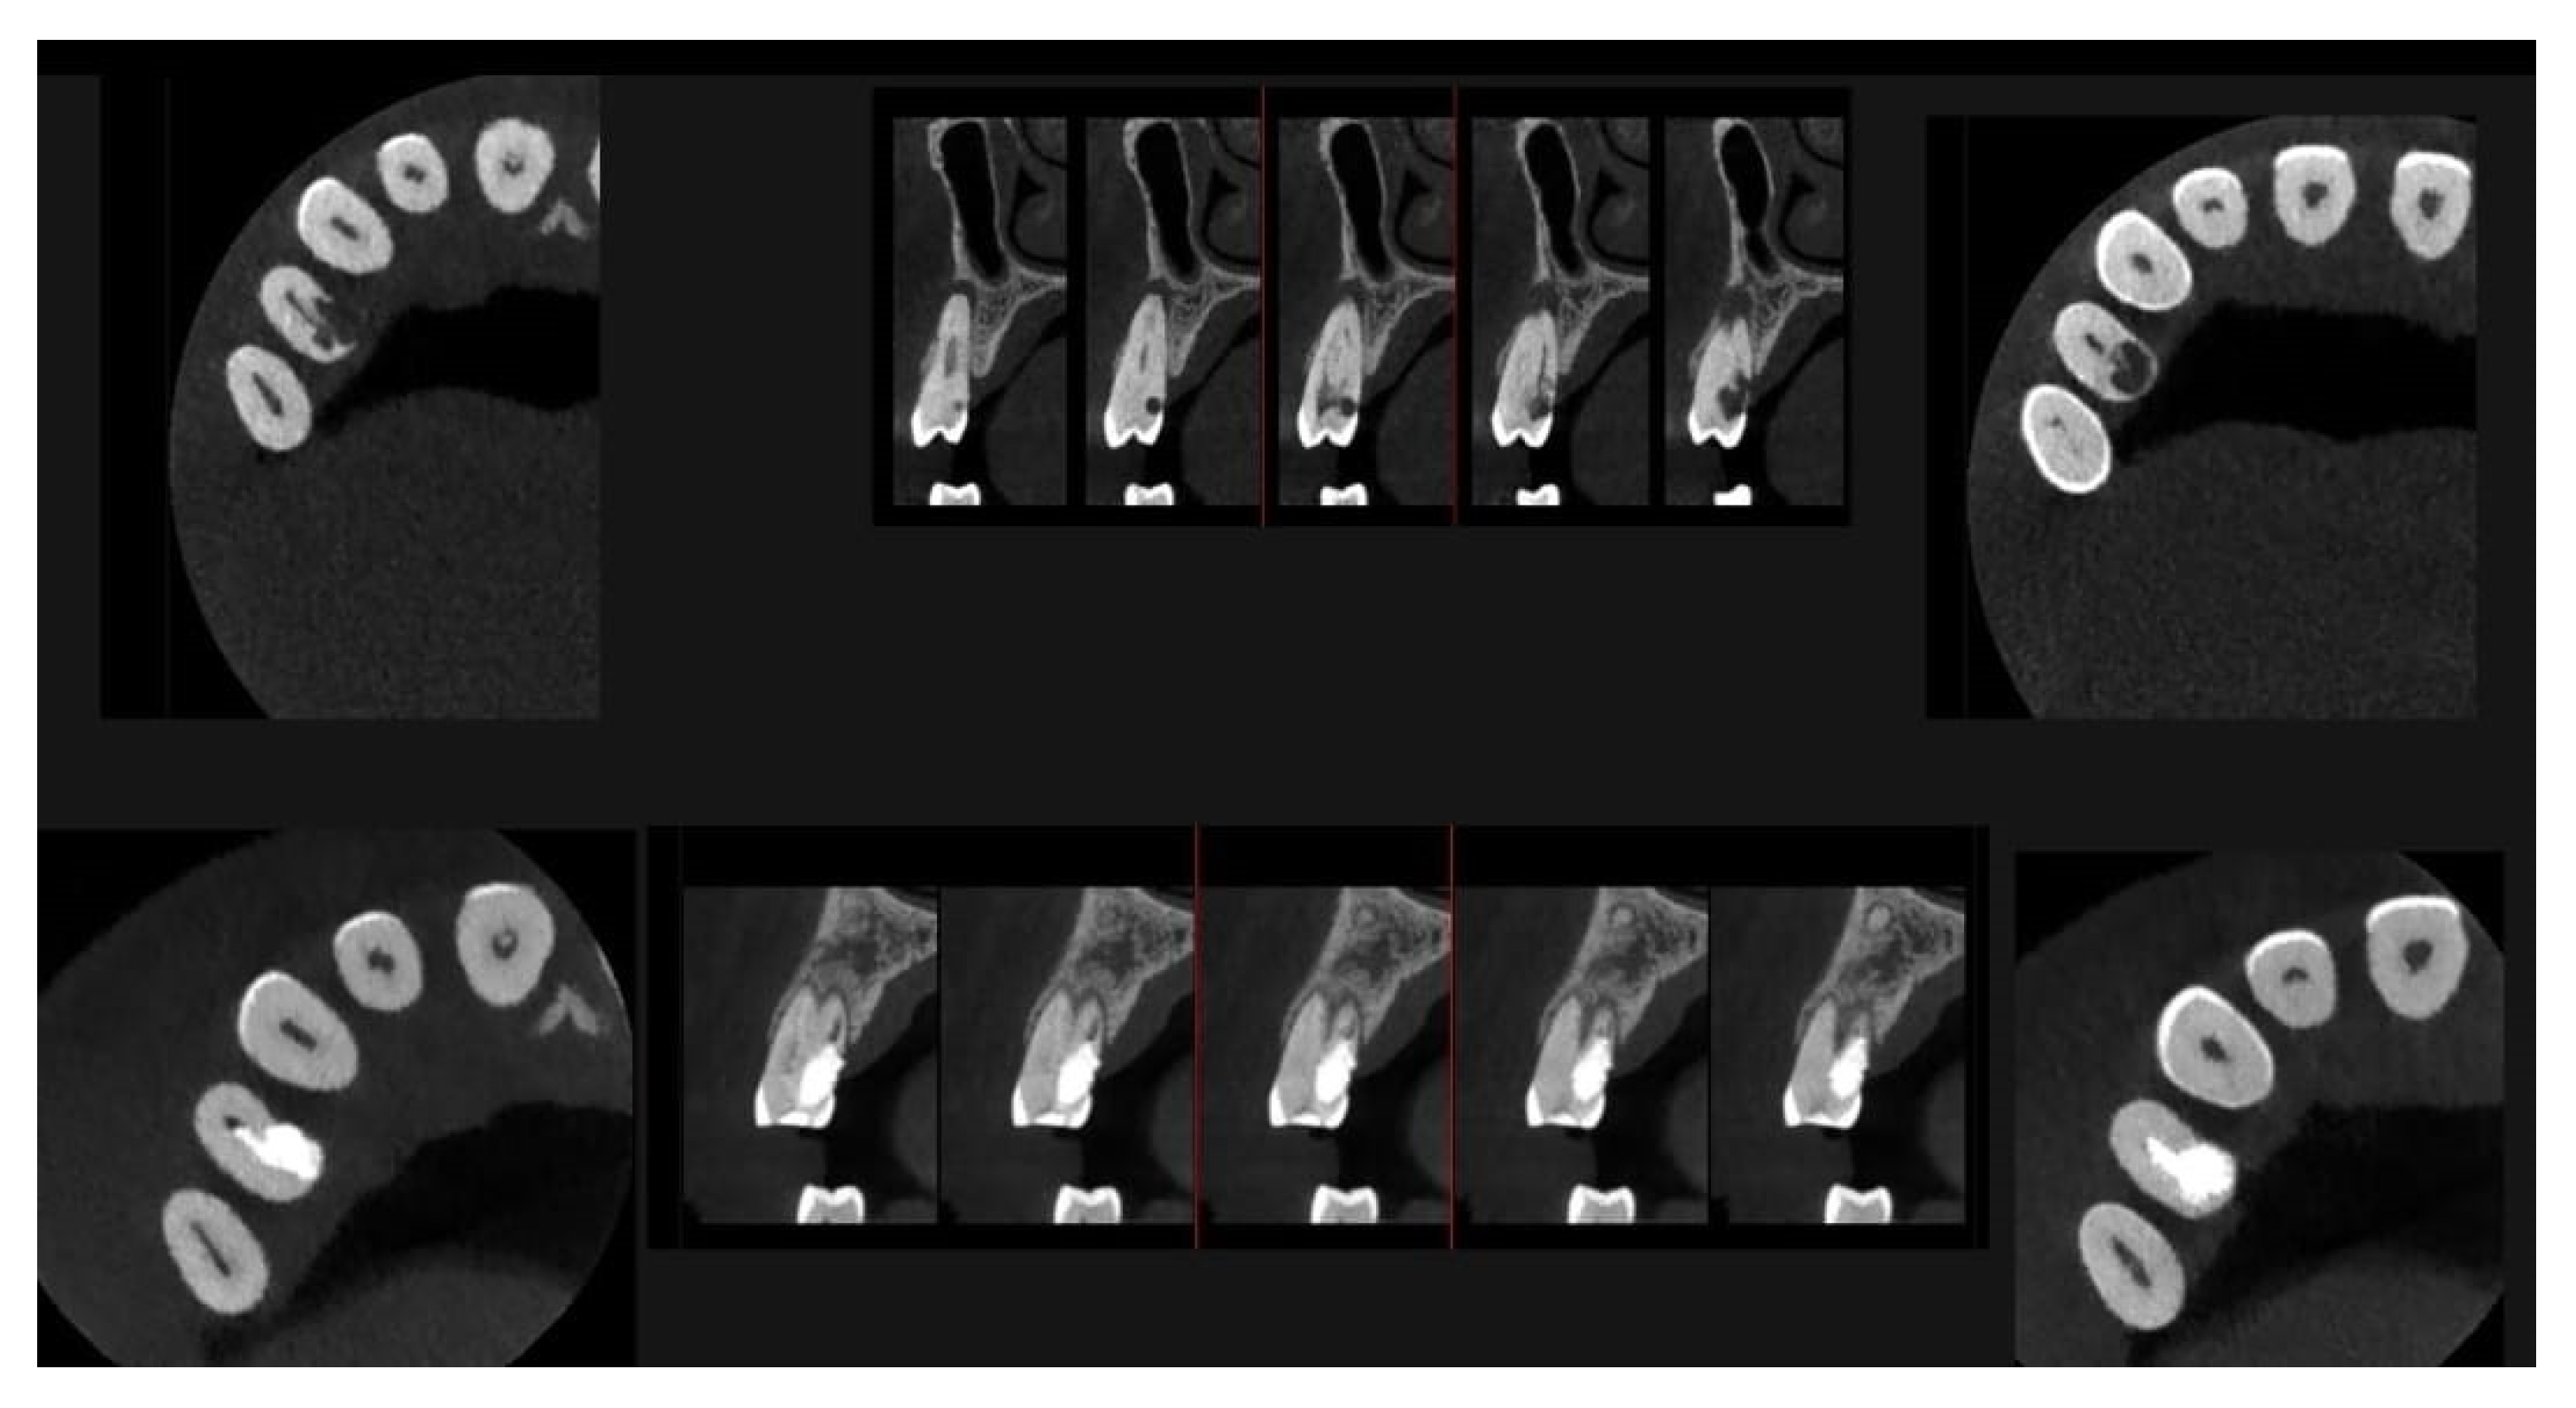

A CBCT examination (X9 Pro®, MyRay, Imola, Italy), performed with dedicated field of view (FOV) (6 × 6) and exposure parameters, was essential for accurate diagnosis and treatment planning. This device optionally features a specific Booster function for users with advanced expertise, which allows for further customization of exposure parameters to optimize the examination more effectively. Optimal management of the FOV, properly centered and limited to the anatomical area of interest, in this specific case slightly extended (6 × 6) to clearly rule out a possible involvement of the maxillary sinus in agreement with the attending otorhinolaryngologist, enabled the acquisition of broader and more detailed clinical and diagnostic information, which is essential in endodontics. Moreover, it allowed for a significant reduction in radiation dose while optimizing spatial resolution [22]. The imaging clarified the extent of the resorption and defined its perimeter, demonstrating an endodontic-periodontal communication, classified as 3Bp according to Patel’s classification [21] (Figure 2, Figure 3, Figure 4 and Figure 5).

Figure 2.

Axial CBCT images of tooth 1.4, showing its ECR and PL. (A–E) Sequential scrolling on the axial plane from the cervical area to the middle third of the root; (F,G) Segmentation of Figure 2E using the advanced software functions iRYS® (MyRay, Imola, Italy); (H,I) Sequential scrolling on the axial plane of the apical third of the root, including the PL.

An intermediate follow-up CBCT scan at 6 months was performed to accurately assess the response to treatment in light of both the extent of the lesion and the patient’s systemic comorbidities (Figure 10, Figure 11, Figure 12, Figure 13 and Figure 14).

Figure 10.

Axial CBCT images of tooth 1.4 after six months of healing. (A–F) Sequential scrolling of the root of tooth 1.4 after six months of healing.

Figure 11.

Cross-section CBCT images of tooth 1.4 after six months of healing. (A–I) Sequential scrolling of EPL healing.

Figure 12.

Pano-rex and cross-sectional CBCT images of tooth 1.4 after six months of healing. (A,B) Sequential scrolling of tooth 1.4 after six months of healing. The colored lines crossing the images represent the orthogonal planes (axial, coronal, and sagittal) in the multiplanar reconstruction. Their correct use and orientation allow for an accurate identification of the extent of the lesions in all spatial planes and a detailed analysis of the endodontic anatomy. The green and red letters are the coordinates of the image: A: anterior, R: right, B: bottom, T: Top.